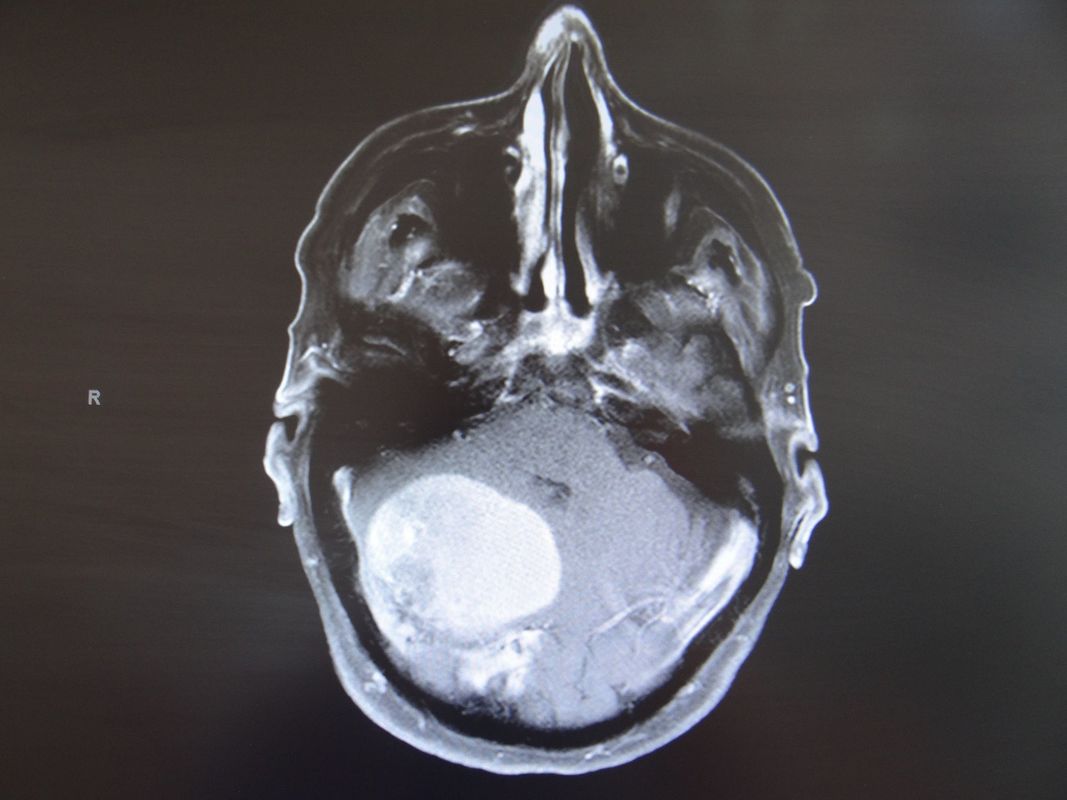

On distingue deux types de tumeurs cérébrales. La première catégorie englobe les tumeurs dites primaires, dont l’origine provient des cellules du cerveau (astrocytes, oligodendrocytes, neurones, cellules épendymaires, cellules méningées). La deuxième catégorie comporte les tumeurs dites secondaires, qu’on appelle plus communément les métastases. Ce sont des tumeurs provenant d’un cancer localisé sur un autre organe du corps. En effet, ces dernières ont la propension de migrer et former une métastase dans le cerveau.

Les tumeurs primaires du cerveau sont divisées en deux sous-catégories : les tumeurs dites intra-axiales, c’est-à-dire qu’elles proviennent des cellules du cerveau (gliomes, épendymomes, neurocytomes,..) et les tumeurs extra-axiales, dont l’origine provient des cellules à l’extérieur du cerveau (méningiome, schwannome,…)

​En général, les tumeurs peuvent être traitées par une craniotomie avec chirurgie d’exérèse et /ou une biopsie quand la localisation ne se trouve pas dans une région profonde du cerveau ou dans une zone « sensible » que l’on nomme fonctionnelle. Le traitement comporte également, dans beaucoup de cas, une radiothérapie et/ou une chimiothérapie.